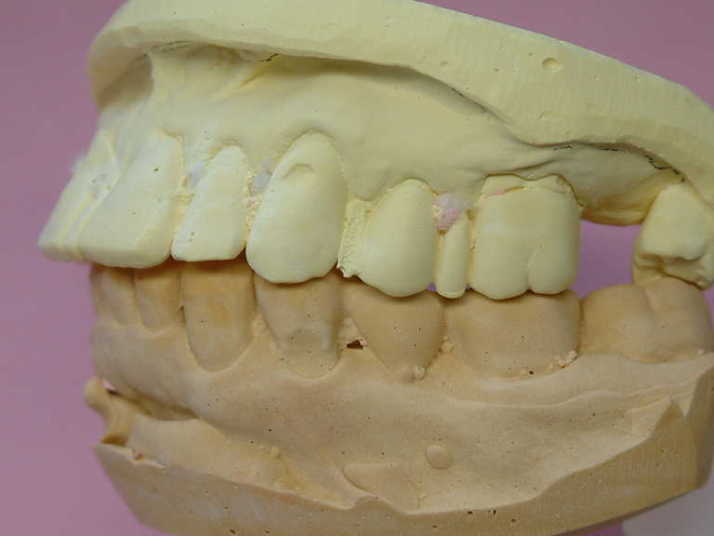

補綴物物 完成

模型上では、1.1下部孤形空隙が広いように

見えますが、歯肉模型にて調整して

歯肉を圧迫せず、息が漏れることが無いように

調整しました |